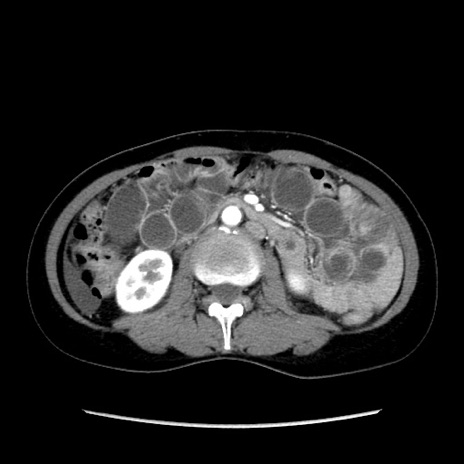

症例32(横断像)

【症例】40歳代 女性

【主訴】上腹部痛、嘔気・嘔吐

【現病歴】約9時間前頃から急に上腹部痛、嘔気、嘔吐が出現。改善しないため救急要請。

【既往歴】子宮頚癌(広汎子宮全摘術、放射線療法)、腸閉塞

【身体所見】腹部:平坦、軟、腸雑音亢進、上腹部を中心に腹部全体に圧痛あり。

【データ】WBC 8400、CRP 0.03